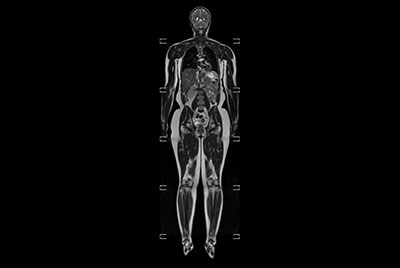

Total Torso with SmartShim

Whole Body imaging under 30 minutes on BlueSeal magnet

Total Torso overview

Total torso and liver

Total Torso imaging - High dS SENSE acceleration

Total Torso imaging - MultiVane XD

Whole Body imaging

Total Body Imaging